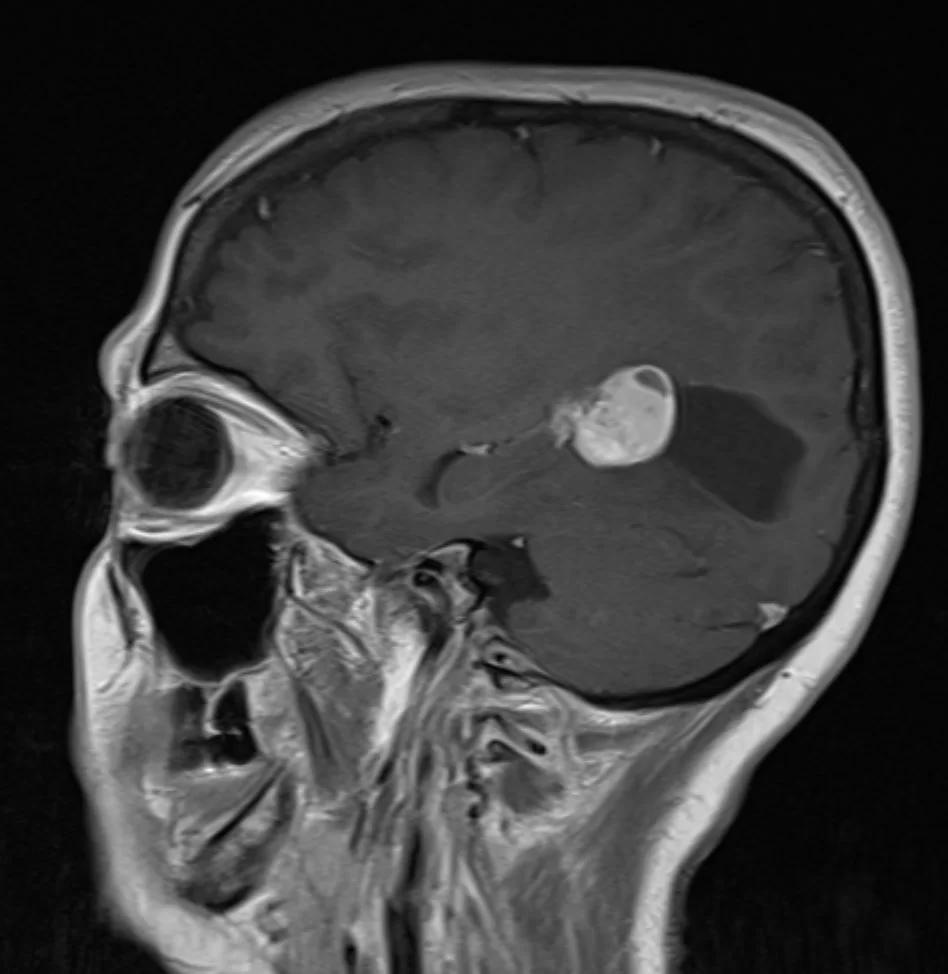

Η μαγνητική τομογραφία ανέδειξε χωροκατακτητική εξεργασία εντός της αριστερής πλάγιας κοιλίας του εγκεφάλου.

Το συγκεκριμένο ενδοκοιλιακό μηνιγγίωμα παρουσιάζει δύο πλεονεκτήματα για τον νευροχειρουργό. Πρώτον, είναι σχετικά μικρό σε μέγεθος και δεύτερον έχει μια κύστη η οποία δημιουργεί «χώρο» τον οποίο μπορεί να εκμεταλλευτεί ο νευροχειρουργός.